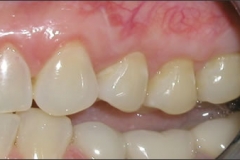

This young patient was self-conscious about the appearance of her short teeth and gummy smile. Through crown lengthening and tooth whitening procedures, we were able to create a beautiful, more mature smile.

Click on a thumbnail to view the before and after photos.